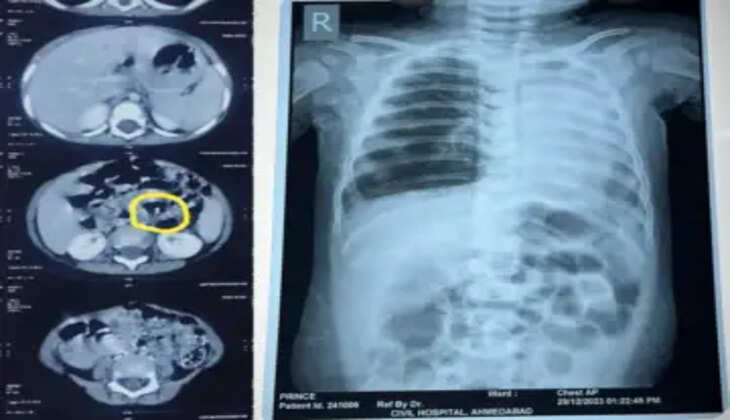

સિવિલ હોસ્પિટલમાં પહોંચ્યાના માત્ર બે કલાકની અંદર જ તેના એક્સ-રેના આધારે ઇમરજન્સી બ્રોન્કોસ્કોપી કરીને ડાબા ફેફસામાં ફસાયેલા સોયાબીનના દાણાને દૂર કરવામાં આવ્યો. સર્જરી અત્યંત જટીલ હતી પરંતુ સિવિલ હોસ્પિટલના બાળરોગ સર્જરી વિભાગના વડા ડૉ. રાકેશ જોષી અને તેમની ટીમે છેલ્લા બે વર્ષમાં અંદાજીત 51 જેટલા આવા બાળકોની બાહ્ય પદાર્થ ગળી જવાની સર્જરી કરી છે. આ બહોળા અનુભવના પરિણામે અને પ્રિન્સની માતા-પિતાની સતર્કતા થી માત્ર બે કલાકમાં જ આ બાળકની સર્જરી કરીને આ સોયાબીનનો દાણો કાઢવામાં સફળતા મળી. હવે બાળક ફરી પહેલાની માફક જ શ્વાસ લઇ શકે છે.

આવો જ એક અન્ય કિસ્સો સિવિલ હોસ્પિટલમાં ડિસેમ્બર મહિનામાં જ બન્યો. જેમાં 2 વર્ષનો યુસુફ નામનો બાળક કે જે અમદાવાદના બાપુનગર વિસ્તારમાં રહે છે તે ટાંકણી ગળી ગયો હતો. આમ જોવા જઇએ તો યુસુફ ના પિતા મોહંમદ કૌસર શેખ વ્યવસાયે દરજી છે , એક દિવસ આ બે વર્ષનો યુસુફ ઇશારા કરીને તેની માતાને કહી રહ્યો હતો કે તે કંઇક ગળી ગયો છે, જેથી તેને પણ શારીરિક સમસ્યાઓ ઉભી થતા માતા-પિતા અમદાવાદ સિવિલ હોસ્પિટલ લઇને દોડી આવ્યા હતા. આ કિસ્સામાં જ્યારે સી.ટી. સ્કેન કરવામાં આવ્યુ હતુ ત્યારે કોઇ બાહ્ય પદાર્થ બાળક ગળી ગયું છે જે મેટલનું છે તેવું સ્પષ્ટ પણે દેખાઇ રહ્યું હતુ. પરંતુ આ કિસ્સામાં મહત્વની બાબત એ બની રહી કે, તબીબોના અનુભવના પરિણામે જ્યારે આ બાહ્ય પદાર્થના ચોક્કસ સ્થાનની ખબર પડી ત્યારે તબીબોના મોનટરીંગ હેઠળ તેને મળ માર્ગે કાઢવાનો પ્રયત્ન કરવામાં આવ્યો . માતા-પિતા ના ધીરજ , બાળકના સહકાર અને તબીબોના અનુભવના લાભથી યુસુફ ને કોઇપણ જાતની સર્જરી કર્યા વિના જ આ મોટા આકારની સોય મળમાર્ગે કાઢવામાં સફળતા મળી હતી.